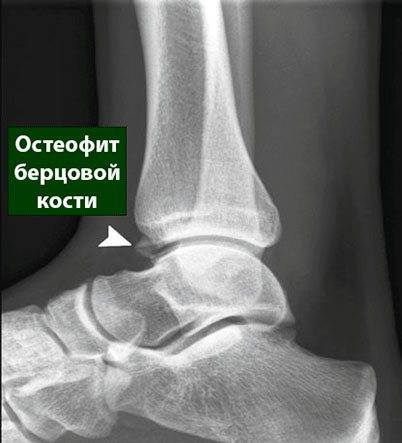

Артроз голеностопа

Суставное сочленение голеностопа — сложное анатомическое образование, которому приходится выдерживать значительные и постоянные нагрузки. В ортопедической практике именно повреждение (артроз) голеностопного сустава занимает ведущее место, более 15% переломов костей скелета приходится именно на долю дистального отдела. При этом около 5% повреждений голеностопа приводят к инвалидности.